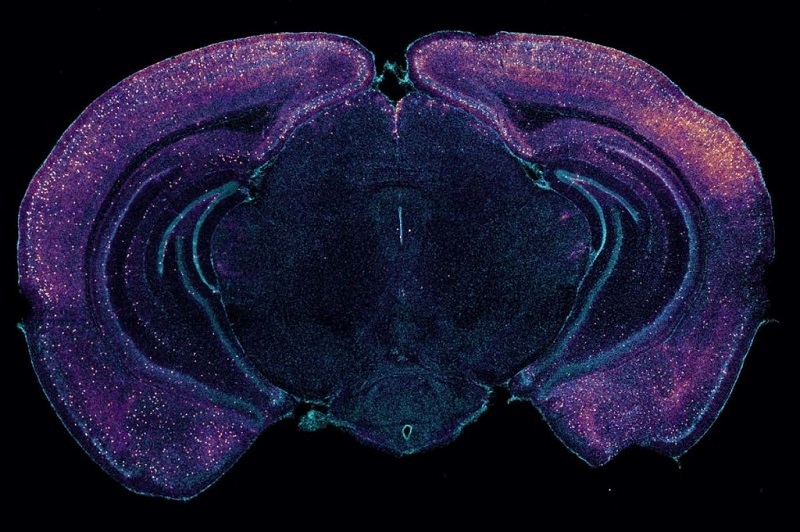

美国科学家最新研究发现,40赫兹的声音和光刺激能增强小鼠大脑清除废物的能力,特别是β淀粉样蛋白等有毒蛋白。这些蛋白会导致记忆和注意力问题。相关论文发表于2月28日出版的《自然》杂志。

小鼠大脑的横截面,显示神经元似乎释放出能更好清除毒素的分子。 图片来源:《自然》网站

此前研究显示,借助声音和闪烁灯光的疗法在阿尔茨海默病小鼠身上显出希望,但其作用机制一直是个谜。2016年,麻省理工学院神经科学家蔡立慧教授领导的团队开始研究40赫兹声光的刺激能否提高阿尔茨海默病患者的认知能力。他们让小鼠每天接受一小时的40赫兹闪烁灯光和声音刺激,结果显示,该方法降低了阿尔茨海默病小鼠大脑内淀粉样蛋白的积累。

在最新研究中,蔡立慧等人在转基因小鼠身上开展了一系列实验,试图揭示该疗法的奥秘。这些转基因小鼠通常会随着年龄的增长产生淀粉样蛋白,记忆力也比普通小鼠差。研究发现,这些特殊的光和声音似乎增强了小鼠大脑的引流系统,即类淋巴系统的功能。

研究显示,当动物暴露在光线和声音中时,其脑内淀粉样蛋白含量会减少。但蔡立慧等人也发现,在治疗过程中,有更多脑脊液进入小鼠脑内,更多废液通过淋巴管排出大脑。原因似乎在于附近的血管脉动更大,有助推动类淋巴液体通过血管;也可能是因为有更多液体流入类淋巴系统。

研究小组还发现,中间神经元这种特定类型的脑细胞似乎通过释放名为血管活性肠肽的分子,增加了淋巴流。当研究小组用化学方法阻断这种分子产生时,声光疗法无法提高淀粉样蛋白的清除率。